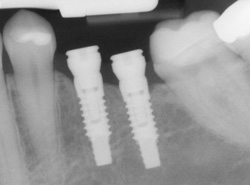

An implant is a new tooth made of steel and porcelain that looks just like your natural tooth. Your implant is composed of two parts that mimic a tooth's root and crown. The implant's "root" is a titanium steel rod placed into the jaw bone to act as a root. Once the rod is in place, a porcelain crown is attached to replace the top part of your tooth.